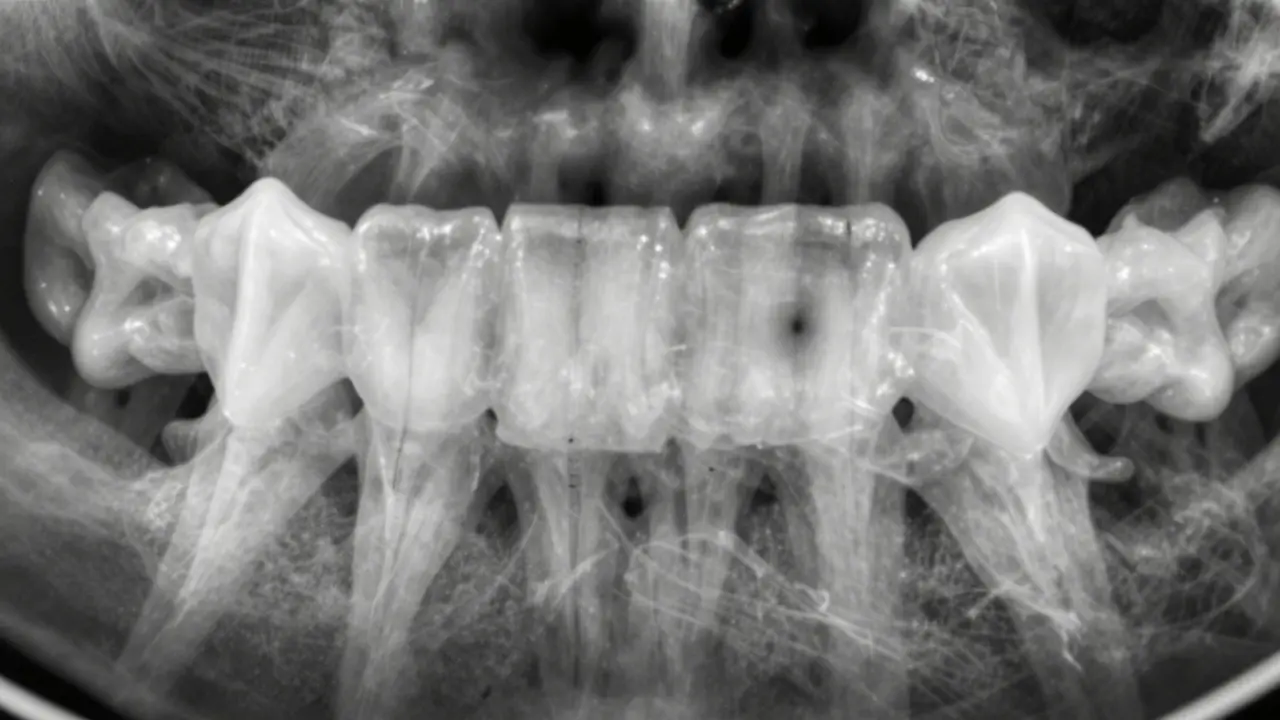

Na rentgenu zubů se zubní kaz nejeví jako černá díra, jak si mnozí představují. Je to jemná, tmavá skvrna, která se často skrývá mezi zuby nebo pod plomby. Pokud jste kdy viděli rentgen svých zubů a nevěděli, co hledat, nejste sami. Většina lidí si myslí, že kaz je vidět hned, když se podívají do zrcadla. Ale skutečnost je jiná - mnohé kazy se rozvíjejí úplně skrytě, až do okamžiku, kdy začnou bolet. Rentgen je ten nástroj, který odhalí problémy dříve, než se stane katastrofou.

Rentgenové paprsky procházejí tělem různě. Kosti a zuby jsou husté, takže je většina paprsků pohltí a na snímku vypadají bělavě. Měkké tkáně, jako je dásně nebo jazyk, jsou průhlednější a vypadají šedivě. Ale když se zubní kaz rozvíjí, minerály v zubní sklovine a dentinu se rozpouštějí. To znamená, že tato část zubu je méně hustá - a proto propouští více paprsků. Na rentgenu to vypadá jako tmavší skvrna v rámci bělavého zubu.

Tato tmavá oblast není vždy stejně velká. U malého kazu to může být jen tenká čára mezi dvěma zuby, která se dá snadno přehlédnout. U pokročilého kazu už je vidět větší tmavá oblast, která se táhne až k zubním nervům. V některých případech se kaz rozšíří pod plombu - a to je přesně ten moment, kdy pacient přijde s bolestí, ale dentista řekne: „Na rentgenu to už je větší problém, než jste si myslel.“

• Mezi zuby (kontaktní plochy) - tady se potraviny zadržují, zubní kartáček nedosáhne, a bakterie vytvářejí kyselinu, která rozežírá sklovinku. Na rentgenu to vypadá jako tenká tmavá čára mezi dvěma zuby, často na straně, kde se zuby dotýkají.

• Pod plombami nebo korunkami - pokud je plomba nekvalitně zasazená nebo se kolem ní vytvořila mezera, bakterie se tam usadí. Na rentgenu se pod plombou objeví tmavá oblast, která se neodpovídá původnímu tvaru zubu.

• U zubních kořenů - pokud máte odsunuté dásně (paradentóza), kořen zubu je vystavený. Tam se může vyvinout tzv. kmenový kaz, který na rentgenu vypadá jako tmavá oblast na špičce kořene nebo podél jeho povrchu.

• Na vrcholku zubu (žvýkací plocha) - zde se kaz objevuje jako malá tmavá skvrna v hlubokých brázdách, které se často vyskytují u molárů. U dětí to často znamená, že se zubní kaz rozšířil rychleji, než se o něj dospělí postarali.

• Zubní kaz na rentgenu vypadá jako tmavá skvrna, ne jako černá díra.